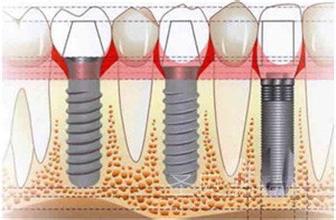

牙齿问题:单颗/多颗牙缺失、半口/全口牙缺失、牙齿松动、假牙不适(点击了解)

▲选择【种植科】(点击进入):即刻种植牙、all-on 4技术优秀解决了顾客牙齿缺失,牙槽骨骨量不足、半/全口植牙费用高等问题。即刻种牙、即刻戴牙,坚固耐用,咀嚼功能颗媲美真牙。 [>>康贝佳即刻种植牙即拔即种即用]